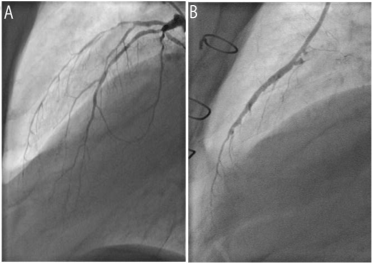

Atherosclerotic Monstrous Double Aneurysm of the Left Main Coronary Artery: A Very Rare Angiographic Finding

Coronary artery aneurysm is a rare disease diagnosed in 0.3 to 4.9% of patients undergoing coronary angiography. The incidence of left main coronary artery aneurysm (LMCAA) is extremely rare: 0.1% [1]. Coronary artery aneurysm involves the right coronary artery, the left anterior descending and circumflex coronary arteries in descending order of frequency [2] and atherosclerosis is the most common cause.